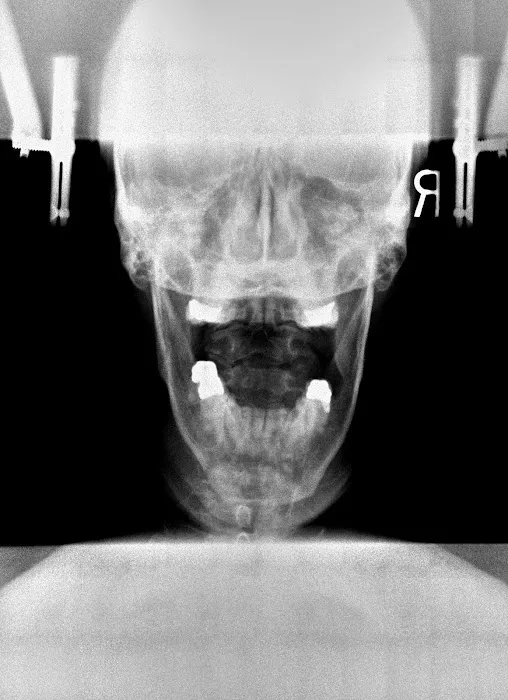

Chiropractic care is a healthcare profession focused on the diagnosis, treatment, and prevention of musculoskeletal disorders, with a primary emphasis on the spine and its impact on the nervous system. While traditional chiropractic often involves manual adjustments that may produce joint cavitation sounds (cracks), specialized approaches like Atlas Orthogonal chiropractic offer a distinctly different experience. This technique focuses on the Atlas vertebra (C1), the uppermost bone in the spine, and its relationship with the skull and the rest of the spinal column. Even a slight misalignment in this crucial area can impact the entire nervous system, leading to widespread issues. Dr. Thomas at Atlas Orthogonal Chiropractic, LLC, utilizes this highly precise, gentle method to realign the Atlas, often without any cracking. This precise adjustment aims to restore proper communication between the brain and body, alleviate pressure on nerves, and allow the body to heal naturally. This approach, combined with other therapeutic modalities, offers a powerful, non-invasive path to relief and long-term wellness.

Atlas Orthogonal Adjustments: This is the cornerstone and specialty of the practice. Utilizing a precise, gentle instrument, Dr. Thomas makes subtle adjustments to the Atlas vertebra (C1), without any twisting, popping, or cracking. This method aims to restore proper alignment of the head and neck, alleviating nerve pressure and allowing the body's natural healing processes to take over.